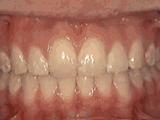

第十种:

深覆盖,咬牙时,上牙差不多完全把下牙挡住了,黄飞鸿的弟子牙擦苏就是这类,经过矫正后的牙齿是这样的~